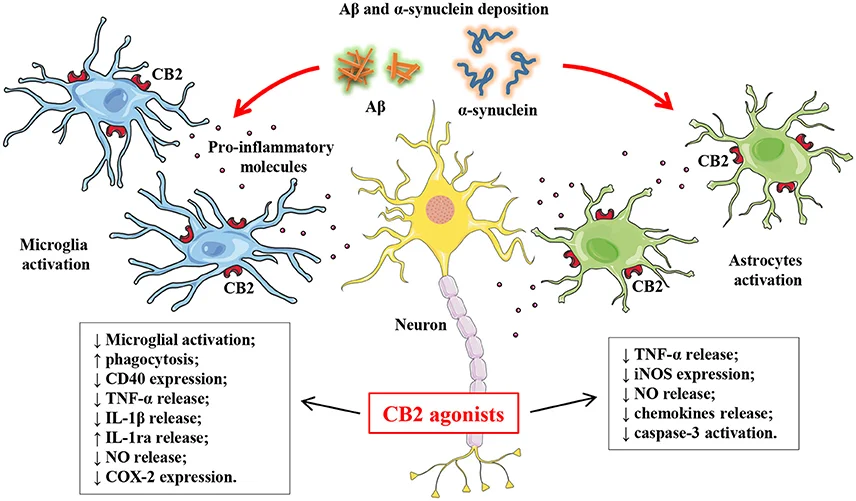

CB2

Good

- Stimulates of opioid receptor. R

- Regulates lipid production and cell death. R

- Inhibit the release of proinflammatory factors. R

- Activation helps Alzheimer's and Parkinson's Disease R

CB2 receptors are expressed in several types of inflammatory cells and immunocompetent cells. R

Activating CB2 receptors inhibit the release of proinflammatory factors. R